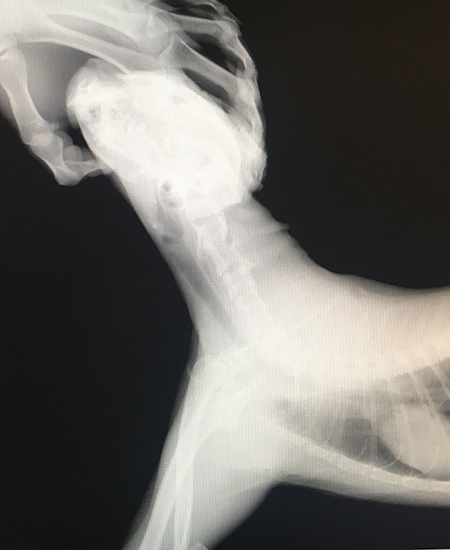

Было принято решение провести рентгенологическое исследование. Снимки выполнены в боковом положении, а также на спине, которые не выявили явных признаков воспаления, а также наличия рентгенокотрастных инородных предметов.

С учетом высокой вероятности наличия инородного тела, связанной с образом жизни кота и наличием характерных клинических признаков, животному перорально было введен бария сульфата. Данное вещество ярко визуализируется на рентгеновских снимках, и позволяет выявить непроходимость желудочно-кишечного тракта, а также окрашивает мягкотканые предметы.

Проведенная серия снимков позволила обнаружить в глотке и пищеводе линейные инородные тела. Для осмотра этой труднодоступной области врач, с согласия владельцев, провел седацию животного, в результате чего удалось обнаружить и извлечь из пищевода части сухой травы. После пробуждения животного ему была выполнена внутривенная инфузия с гастропротекторами, обезболивающая и противовоспалительная терапия. Кот был выписан домой для дальнейшего лечения и восстановления. После проведенных процедур животное полностью восстановилось.